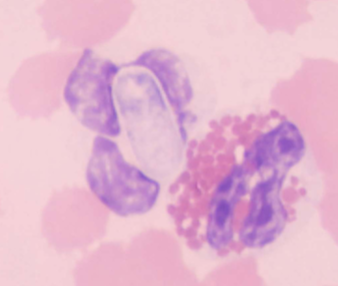

How do you identify Hepatozoon spp.: H. canis and H. americanum

INTRAcellular – malaria-like pill-shaped inclusions inside neutrophils and monocytes (WBCs)

what are the 2 forms of Hepatozoon spp.: H. canis and H. americanum

Gamonts and Schizonts

What does Hepatozoon spp.: H. canis and H. americanum cause

Subclinical to fever, depression, and bone disease